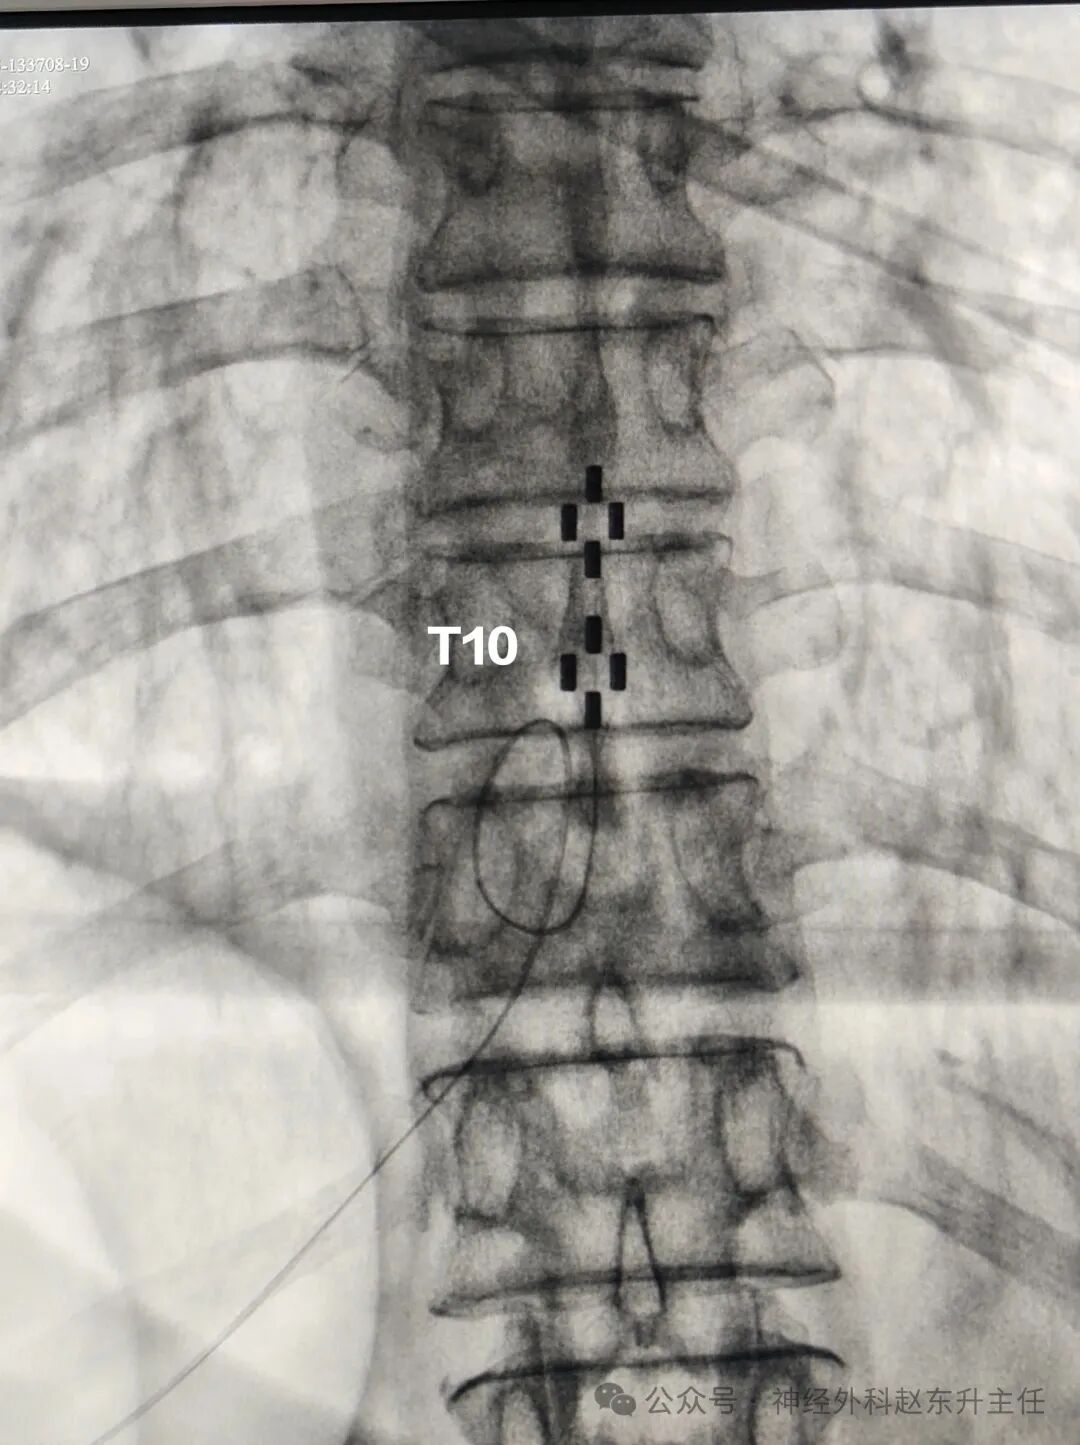

IMG_20250515_151024.jpg

IMG_20250515_151109.jpg

骶神经电极位置